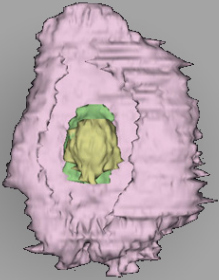

0 μm

Carnegie Embryo #8020 | Location: 06-02-05

Keywords: amnioblast(s), blastocystic cavity (blastocoele), cytotrophoblast, embryonic disc, endometrial sinusoid, lumen of endometrial gland, membranous trophoblast at abembryonic pole, solid syncytiotrophoblast, uterine cavity

Source: The Virtual Human Embryo.